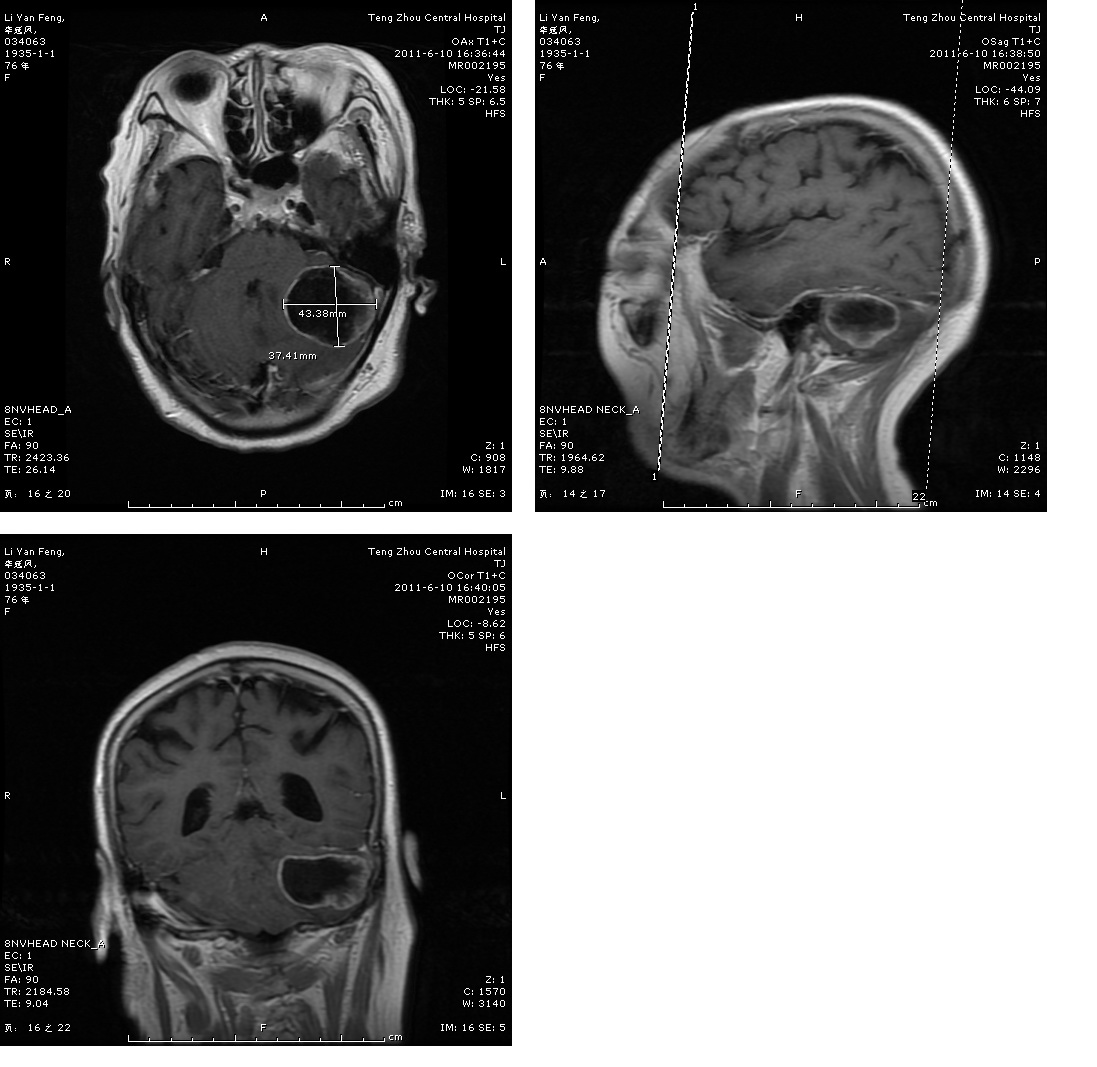

转移瘤切除术前

转移瘤切除术后